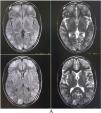

ResultsCase 1: posterior reversible encephalopathy syndrome (PRES)A 24-year-old previously healthy woman presented with fever and headache for the last seven days, for which she was taking acetaminophen without any resolution. For the last three days, she has had recurrent episodes of vomiting and vision difficulties. On admission, she was febrile with relative bradycardia; vital parameters, including serial blood pressure measurements, were within normal physiological ranges. General physical examination failed to identify any eschar or any other clue to aid in diagnosis. Neurological examinations were grossly unremarkable except for terminal neck rigidity, Brudzinski’s sign, mild photophobia, and papilledema.

Complete blood cell counts showed leukocytosis (12 900/µL) with normal platelet count and raised erythrocyte sedimentation rate (24 mm in the first hour). Liver and renal function were normal. Brain magnetic resonance imaging (MRI) revealed asymmetric bilateral T2-weighted (T2-WI) and T2-fluid-attenuated inversion recovery (FLAIR) sequences hyperintensities in the parietooccipital and frontal region with patchy diffusion restriction, suggestive of vasogenic edema (PRES) (Fig. 1). 1–70 Hz electroencephalogram was normal and cerebrospinal fluid (CSF) studies revealed lymphocytic pleocytosis (26 cells, all lymphocytes), low glucose (26 mg/dL), and raised protein (85 mg/dL). Detailed investigations for febrile illness were negative for typhoid, malaria, leptospira, dengue, and chikungunya infections. Hepatitis A, B, C, and D status were negative. However, scrub typhus was diagnosed by IgM ELISA and later confirmed by an immunochromatographic card test method. Qualitative-polymerase chain reaction (PCR) in the CSF ruled out relevant neuro infections. Hence, scrub typhus infection associated with PRES was considered. Intravenous doxycycline (200 mg/day) was administered in two divided doses, followed by doxycycline 100 mg twice a day for four weeks. Since the eighth day of antibiotic therapy, she remained afebrile and was discharged asymptomatic after ten days. A follow-up brain MRI was performed four weeks later and showed complete resolution of the brain lesions.

Case-based discussionsCase 1: PRES, a potentially reversible clinical-radiological syndrome caused by a breach in the blood-brain barrier, leading to capillary leakage into the surrounding interstitium,18 is extremely uncommon in scrub typhus.19,20 During the COVID-19 pandemic, discussions on infection-associated PRES have gained some momentum.21 From existing knowledge of infection-associated PRES cases, it can be presumed that PRES in scrub typhus arises as a result of a) infection-related septic shock and dysregulation of the cerebral blood flow, or b) direct endothelial damage and vasogenic edema secondary to the infection-induced systemic inflammatory state and associated cytokinemia.18–21 The second mechanism is likely to have occurred in our case as there was no change in blood pressure levels during the hospital stay.